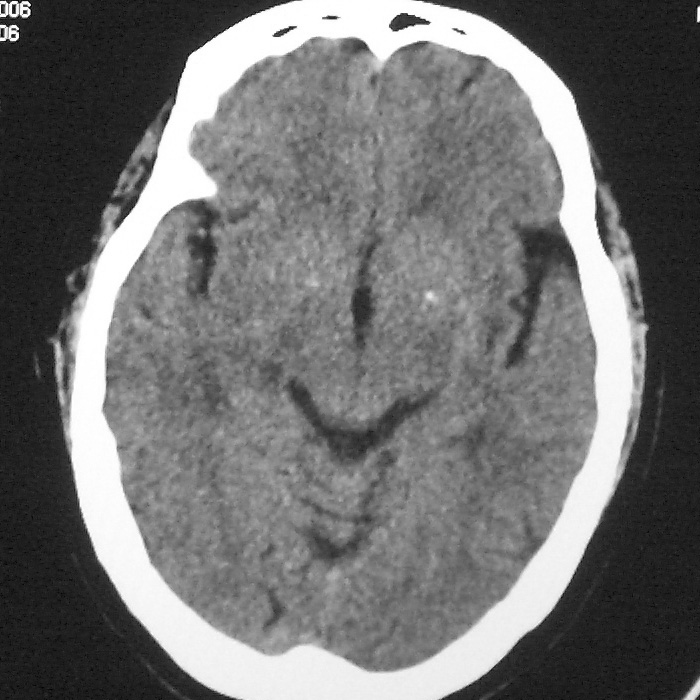

f,70y,口角歪斜、流涎、吐词不清三天

左侧大脑基底节区点状低密度影,边缘清楚,左侧腔梗或软化灶,没什么问题啊?

症状这么明显的话一般不会是单纯面神经麻痹引起的,最好做个mri,如果确实没有问题的话才能考虑面神经麻痹,毕竟这两种病的治疗和预后不一样,这个病人还有脑白质疏松。

左侧半卵圆中心腔梗应当比较明确,右侧基底节好象不明显,不好说,做个mri明确吧

双侧多发腔梗

右侧基底,左侧半卵圆中心腔梗

1、右侧基底,左侧半卵圆中心腔梗。2脑萎缩。

左侧腔隙性梗塞灶,脑萎缩。

左侧基底节区示点状低密度灶,边界清楚,密度均匀,余所示无著变。

意见:腔隙性脑梗塞(左基底节区)

各位老师,报告这么写可以吗?右侧我没有看出来。

左侧半卵圆中心,右侧基底节腔梗。再加个脑萎缩吧

双侧多发腔梗 脑萎缩